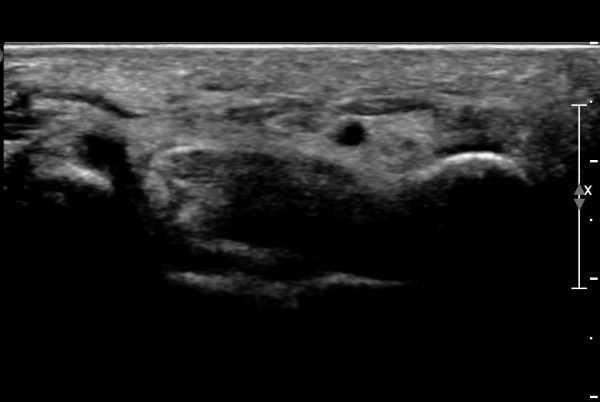

ŽÃËÀÚ¸¦ ¾à°£ ¸»´ÜÀ¸·Î À̵¿ÇÏ´Ï ¿¬ºÎÁ¶Á÷ ºÎÁ¾ÀÌ ´õ¿í ½ÉÇÏ°Ô °üÂûµÇ°í(»çÁø 2),

Á¶±Ý ´õ ¸»´ÜÀ¸·Î À̵¿ÇÏ´Ï Äá¾Ë»À ÇÇÁú°ñ ¿¬¼Ó¼º ¼Ò½ÇÀÌ °üÂûµÊ(»çÁö 3),